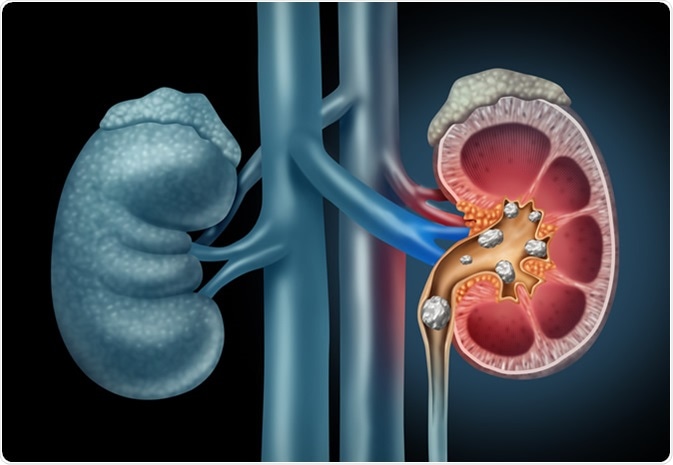

Kidney stones

Kidney stones form when there is a decrease in urine volume or an excess of stone-forming components in the urine. A kidney stone may not cause any symptoms unless it moves around within the kidney and passes down in the ureter. Severe pain may then occur in the side and back, below the ribs, and can radiate to the lower abdomen and groin area.

Human Kidney stones medical illustration. Image Credit: Lightspring / Shutterstock